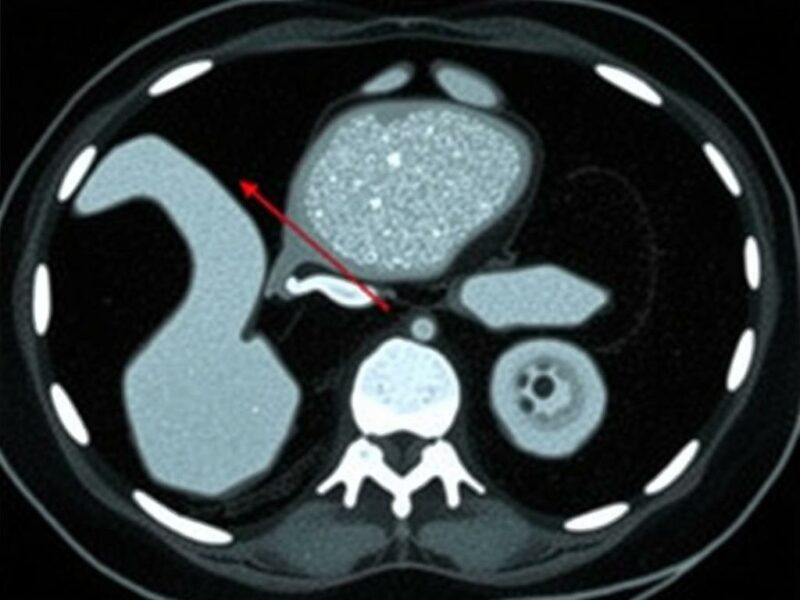

El signo más clásico es la dilatación del apéndice por encima de un diámetro umbral (frecuentemente >6 mm). Un apéndice no comprimible, de diámetro aumentado, con pared engrosada y pérdida de la transición mural es altamente suggestivo de apendicitis. El realce mucoso o mural tras contraste refuerza la sospecha. Otro hallazgo directo es la presencia de un fecalito intraluminal hiperdenso: su visualización dentro de un apéndice dilatado y con signos inflamatorios periféricos aumenta la probabilidad de apendicitis obstructiva.

Es importante recordar que el criterio numérico (por ejemplo, >6 mm) debe interpretarse en contexto: un apéndice distensible por gas puede ser mayor sin inflamación, y variaciones anatómicas pueden alterar la medida. Por eso la combinación de diámetro aumentado con signos inflamatorios periapendiculares logra la mejor precisión diagnóstica.

- Fecalito intraluminal hiperdenso.

| Fecalito | Foco hiperdenso en el lumen que sugiere obstrucción. | Asociado a mayor probabilidad de aposo o perforación. |